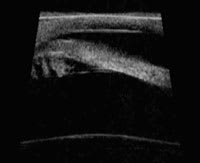

| Heidelberg slit lamp OCT of the anterior chamber angle. |

The Stratus OCT (Carl Zeiss Meditec), used clinically for the evaluation of the retina, employs a 0.8 nm wavelength that cannot penetrate the sclera. As such, it is not ideal for assessing the anterior segment. However, the anterior segment version, the SL OCT, uses a longer wavelength that produces clinically useful results. Preliminary clinical studies suggest that anterior segment OCT compares favorably with conventional gonioscopy in its ability to identify potentially occludable angles.

The SL OCT allows for precise evaluation, measurement and analysis of the anterior segment, including anterior chamber depth (ACD), anterior chamber angles and the angle-to-angle distance (anterior chamber diameter). It can also assist in postoperative evaluation because it allows imaging and measurement of intraocular lenses and ocular implants.

The procedure is relatively fast. Additionally, you can perform it in complete darkness as well as in brightly lit surroundings (to assist in the dynamic assessment of the angle). The images are also digitally documented, so you can magnify, enhance, transmit and measure them. In addition, a technician can take the image, freeing the doctor to focus time on assessing the results. Compared with existing technology (ultrasound biomicroscopy), the anterior segment OCT does not contact the eye and provides a higher resolution image.